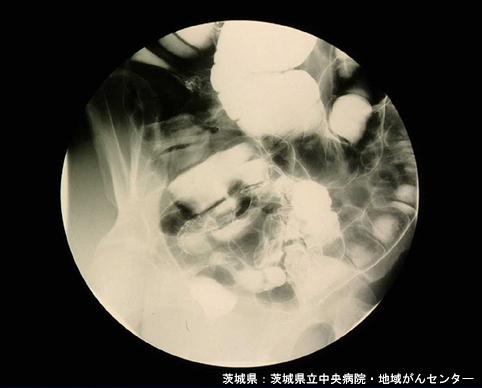

clasificación del pacienteLesión que asemeja tumoración/Endometriosis

parte(separada por órganos)colon/recto

método de exámenRayos X

diámetro mayor del tumor40 -